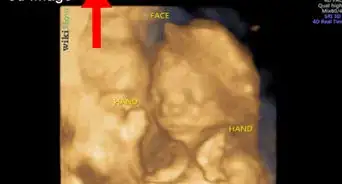

5Lay still and breathe normally as the doctor palpates your uterus. Before the actual measurement takes place, your doctor or his nurse or midwife will palpate your pregnant uterus to determine the baby's size, the baby's positioning and the baby's presentation.

- The doctor, nurse, and/or midwife will also check the volume of amniotic fluid and also attempt to identify the uterine fundus - the point on your stomach where the "top" of the uterus can be felt.

6Allow the doctor to measure your fundal height. After the palpation, the doctor will hold a metric-based measurement tape at the top of the uterus (or fundus) and stretch it along the top of your pregnant uterus, measuring along the longitudinal axis.

- This means that the doctor will measure from the highest point of your uterus to the top of your symphysis pubis (the area located below your belly button where your pubic bone begins). The doctor will record your fundal height measurement in centimeters and enter it on your chart.